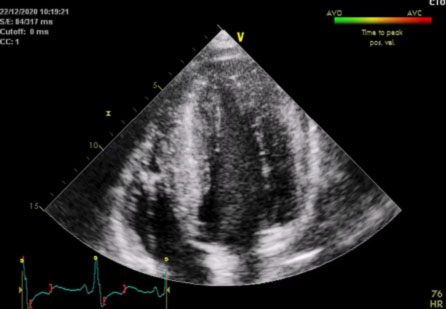

La sindrome di Noonan

“Trattiamo le aritmie cardiache dallo studio dei geni all’ablazione transcatetere“